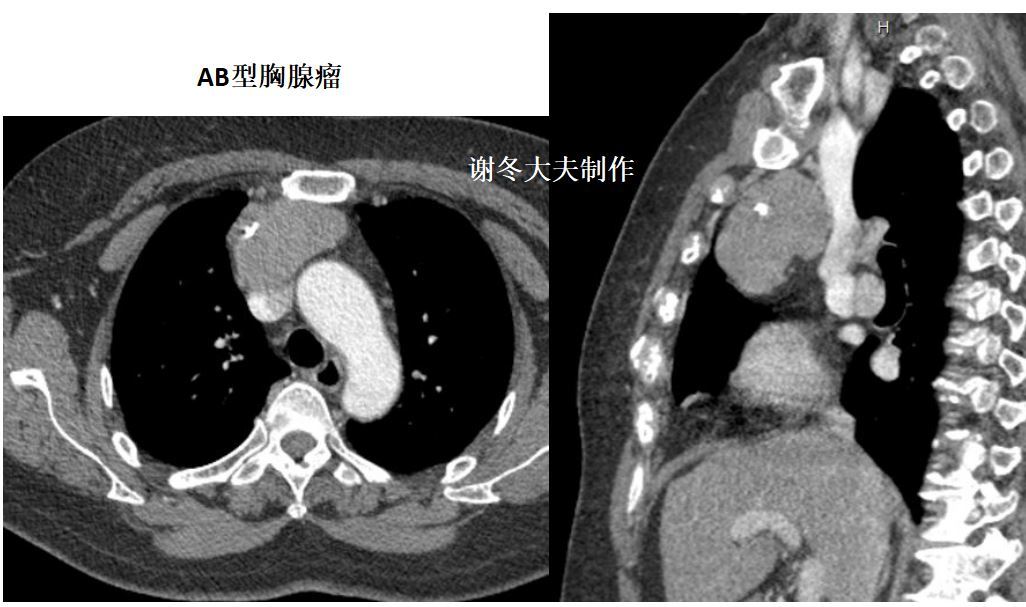

1.非侵袭性胸腺瘤:

圆形、卵圆形或分叶状肿块;边界清晰;多数密度均匀,也可发生囊变;大部分肿瘤生长不对称,居于前纵隔的一侧;

直径<2cm的胸腺瘤可仅表现为正常胸腺边缘局部隆起。